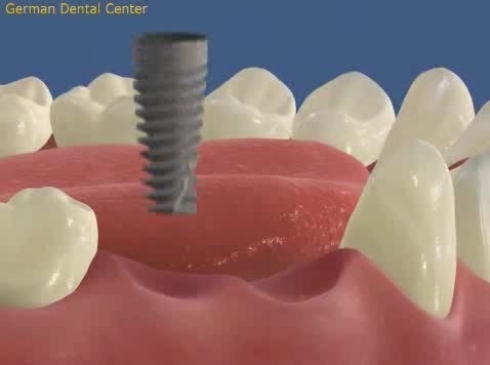

- Имплантация